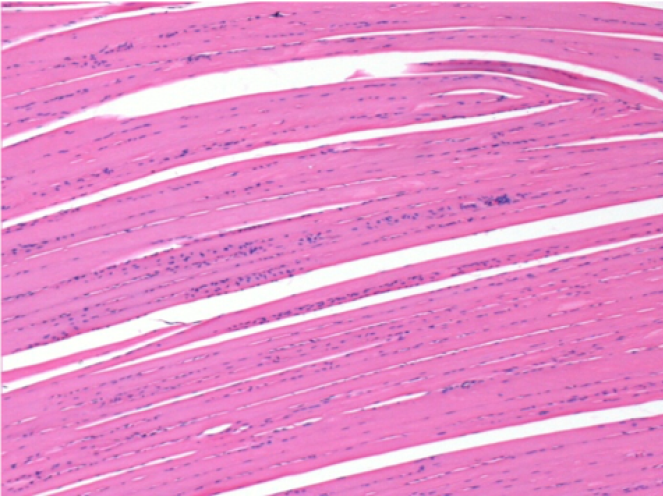

0,5 мл (5x 0,1 мл) підшкірна ін'єкція Ендопіл в праву підшкірну претибіальну ділянку.

Л:200x-Контроль-ПШ

П-10днів-ПШ-200X

П-30днів-ПШ-200X

П-90днів-ПШ-200X

П-210днів-ПШ-200X

П-210днів-ПШ-400X